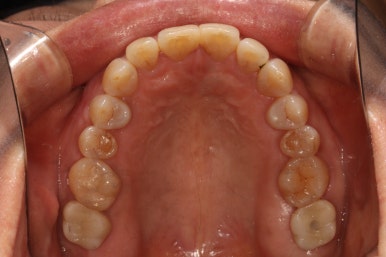

왼쪽: 위턱, 오른쪽: 아래턱

위턱과 아래턱의 교합면 사진입니다.

아래턱 사진을 보시면 치아가 하나 비어있는 것을 아실 수 있죠? 두 개 비어보이시겠지만, 하나는 사랑니니깐 한개로 칩니다. 아까 치과용 파노라마에서 빨간색 동그라미!

위턱 사진을 보시면 뿌리만 있는 치아를 확인하실 수 있을거에요. 노란색 동그라미!

마지막으로 딱 한개 있는 금니를 보실 수 있을텐데, 이차 충치가 있어 다시 치료해야했던 치아입니다. 파란색 동그라미!

왼쪽 : 위턱, 오른쪽 : 아래턱

마지막으로 위턱 아래턱 교합면 사진입니다.

아래의 치료 전과 스크롤을 올리고 내리면서 비교해보시면 확실히 개선된 상태임을 확인하실 수 있어요.

치아가 없던 자리에 자연스러운 흰색의 지르코니아 크라운을 갖는 임플란트가 생겼고,

이차 충치가 있던 금니도 새로이 제작된 지르코니아 크라운으로 잘 사용하고 있으신 상태입니다.

사랑니가 없어져 더욱 개선된 구강위생관리도 확인할 수 있었습니다!